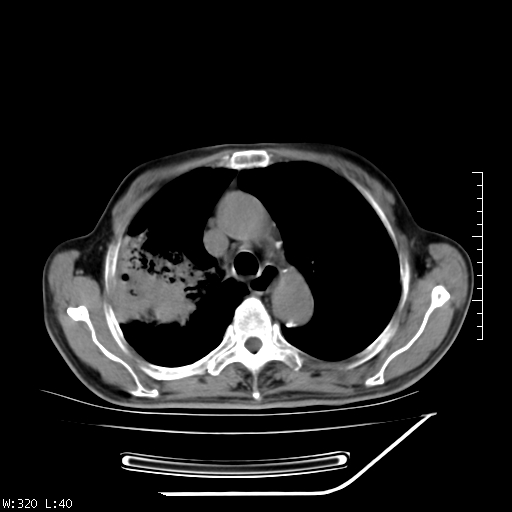

标题: CT23994:男、72、咳嗽、气短两月余,近来消瘦。 [打印本页]

标题: CT23994:男、72、咳嗽、气短两月余,近来消瘦。

右上肺实变,与胸膜关系密切,右肺容积缩小,隆突下淋巴结增大,考虑1 肺结核 2 肺癌

右上肺大片状密度增高影,与胸膜关系密切,内见低密度透亮影,胸膜下可见三角形不张影,左下肺沿支气管走形结节影,纵膈内淋巴结显示。考虑结核并疤痕性不张可能性大,建议穿刺活检,排除肺泡癌。